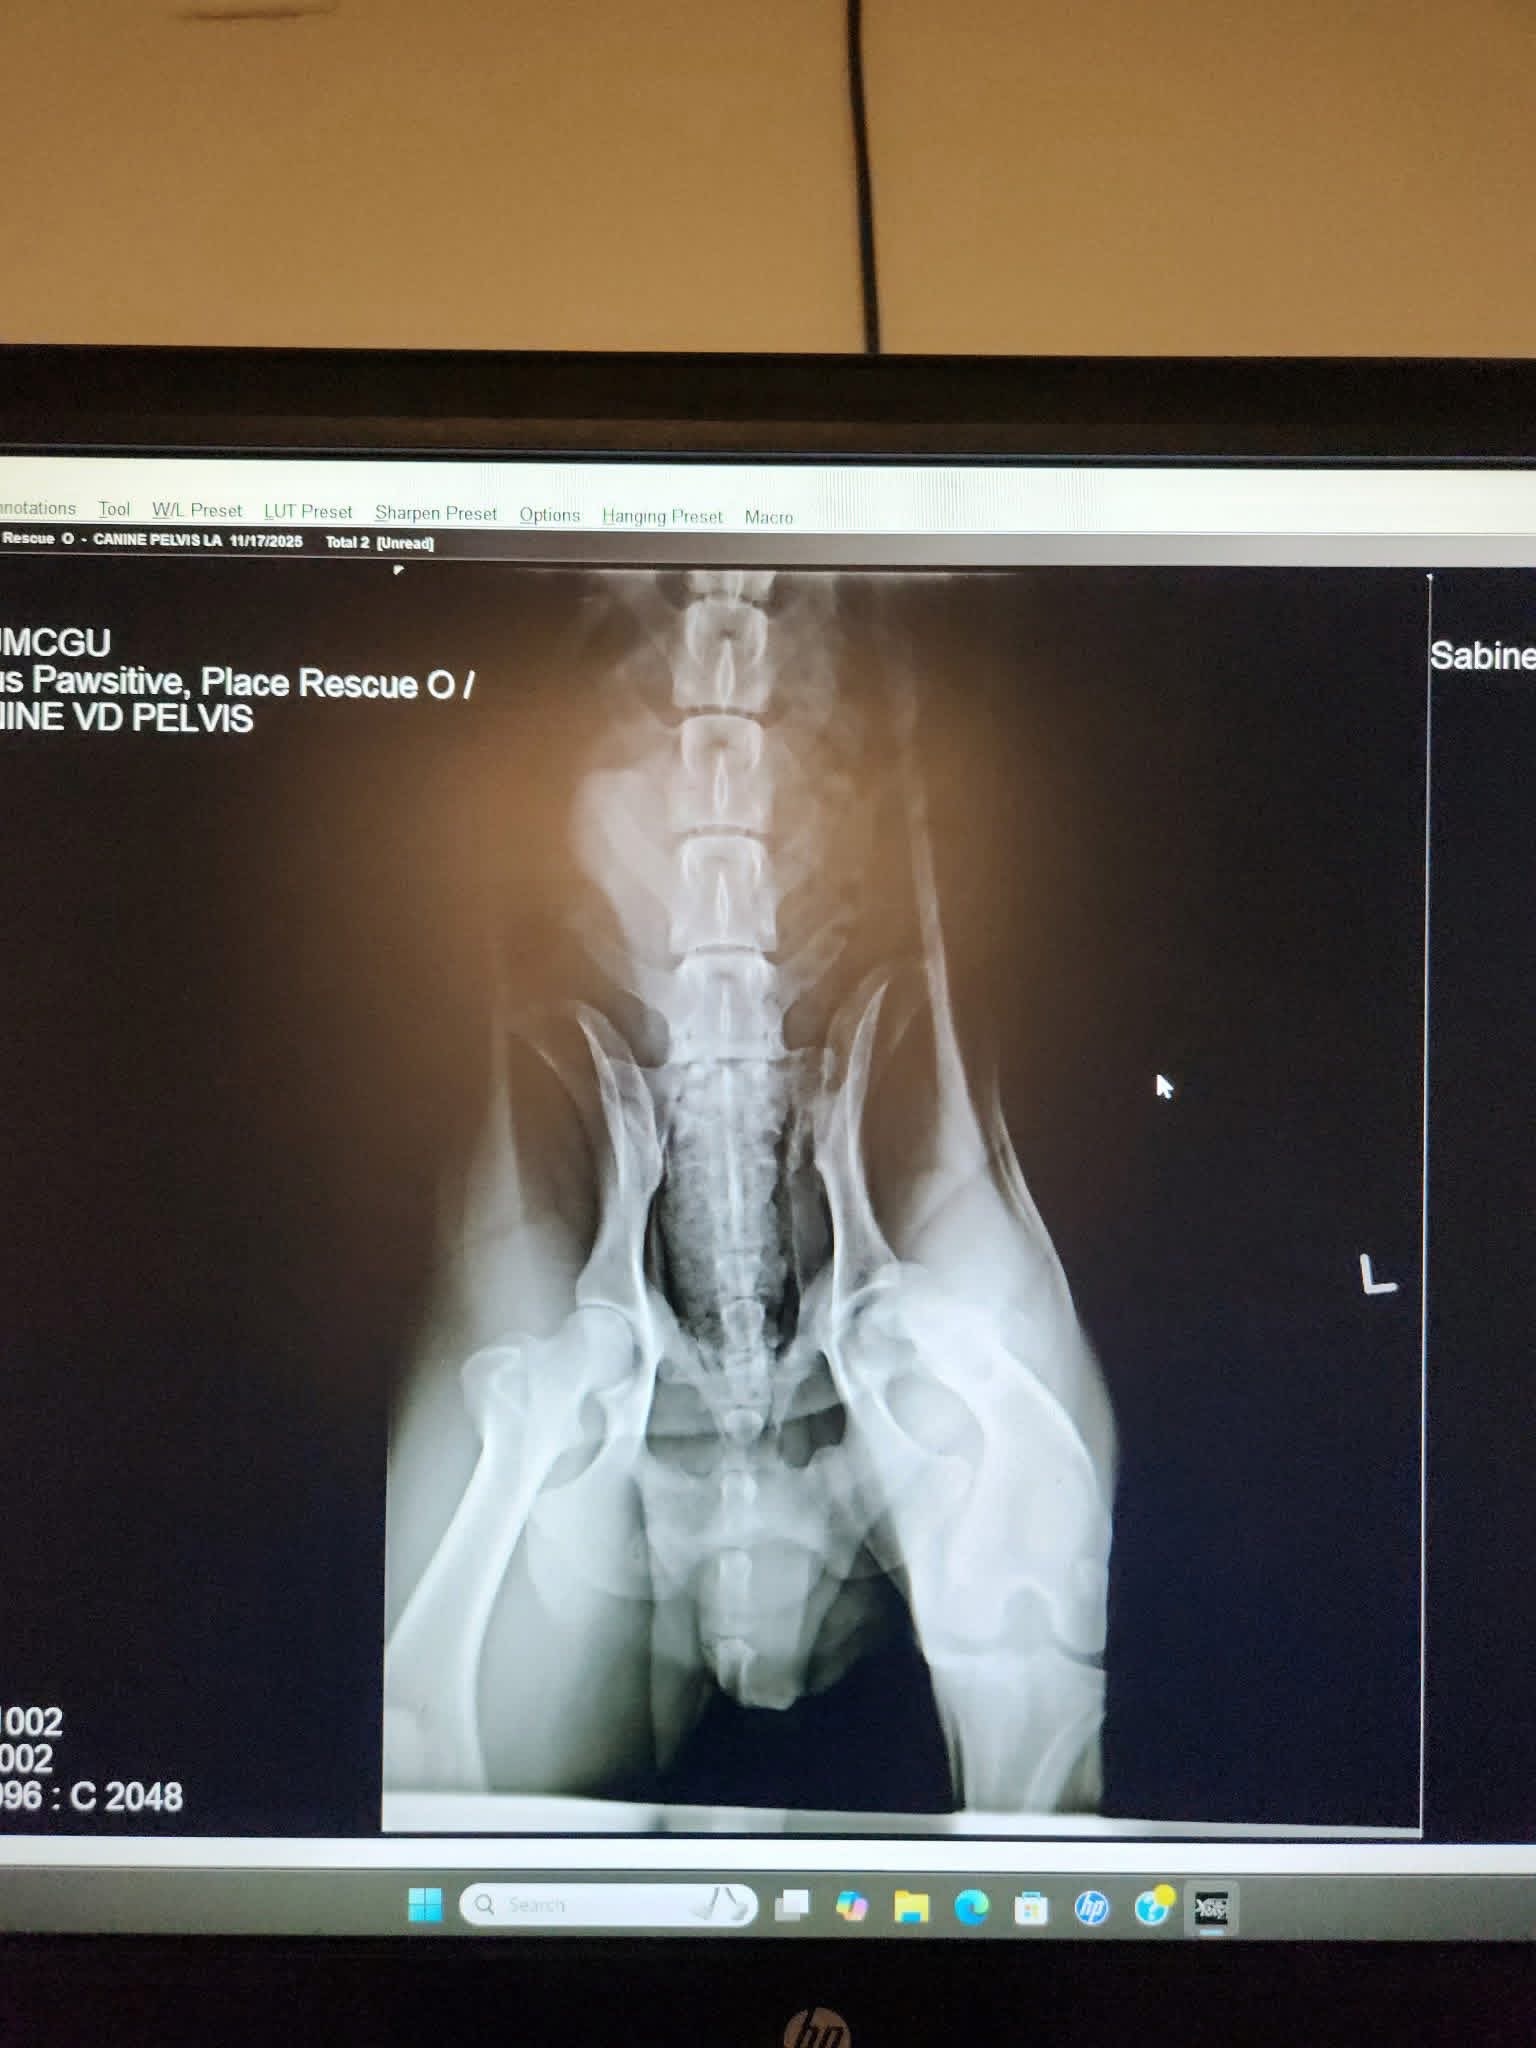

Today is Giving Tuesday, and it’s a day that reminds us why we do what we do. This summer, many of you helped us save Remington after he was hit by a car — and because of the strength of this incredible community, he’s now living his happiest life. Today, we are asking for that same love for Ringo. Ringo was hit by a car, leaving him with severe injuries and in immense pain. His previous caretaker, unable to afford the urgent medical care he needed, was heartbreakingly considering euthanasia. No dog should ever face losing their life simply because treatment is too expensive. We stepped in to make sure Ringo got a fighting second chance. After an emergency assessment with lots of x-rays, it’s clear that Ringo urgently needs a left back leg amputation as well as surgery to repair a broken tibia on the opposite leg. Without these procedures, he cannot walk, rest comfortably, or live anything close to a pain free life. Your support is what makes these miracles possible. Truly we can’t do this without you. If you’re able to give today — or even just share this post — it means the world to us and to Ringo. Please keep him in your prayers and send a little love his way